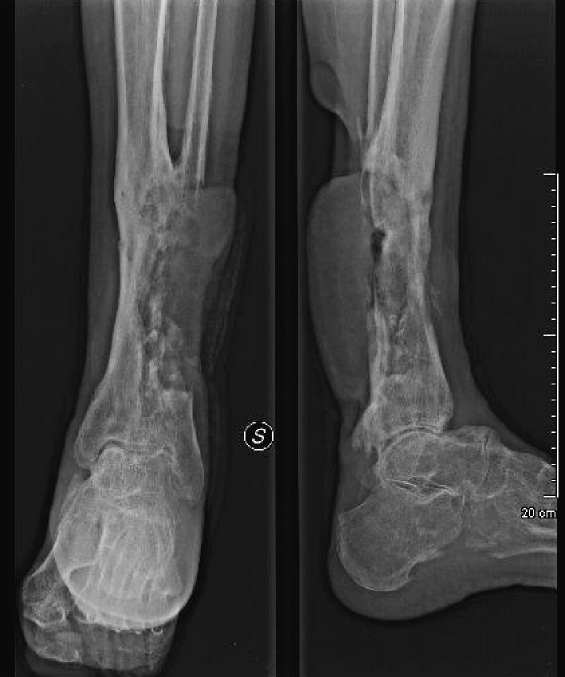

Figure 1. Chronic osteomyelitis of the distal portion of the left leg of our patient. The X-ray image shows a structural bone alteration of the distal tibia, with areas of bone rarefaction close to areas of bone sclerosis due to the sequelae of the inveterate osteomyelitic process. Inside the osteomyelitic areas, a remarkable osteolysis is appreciable, which leads to the disappearance of the distal portion of fibula, and that of the cortical, posterior-lateral tibial margins, attributable to the invasion by the overwhelming SCC of the skin.

At the time of hospitalization in our Department of Infectious Diseases, the patient suffered from a severe local pain, and presented enlarged ulcerations with a necrotic basis and abundant malodorous secretions at his left leg, in absence of fever and systemic signs and symptoms. Antibiotic treatment included i.v. piperacillin-tazobactam at 18 g/day, plus levofloxacin 500 mg, two times a day. The intense pain was poorly controlled by opioids, plus paracetamol, and gabapentin for paresthesia. A computerized tomography (CT) of the left leg disclosed a remarkable rarefaction of bone tissue, especially of the peroneal one, which contraindicated an eventual bone reconstruction. The underlying neoplastic complication was already suspected by a conventional X-ray study of the limb (Figure 1).